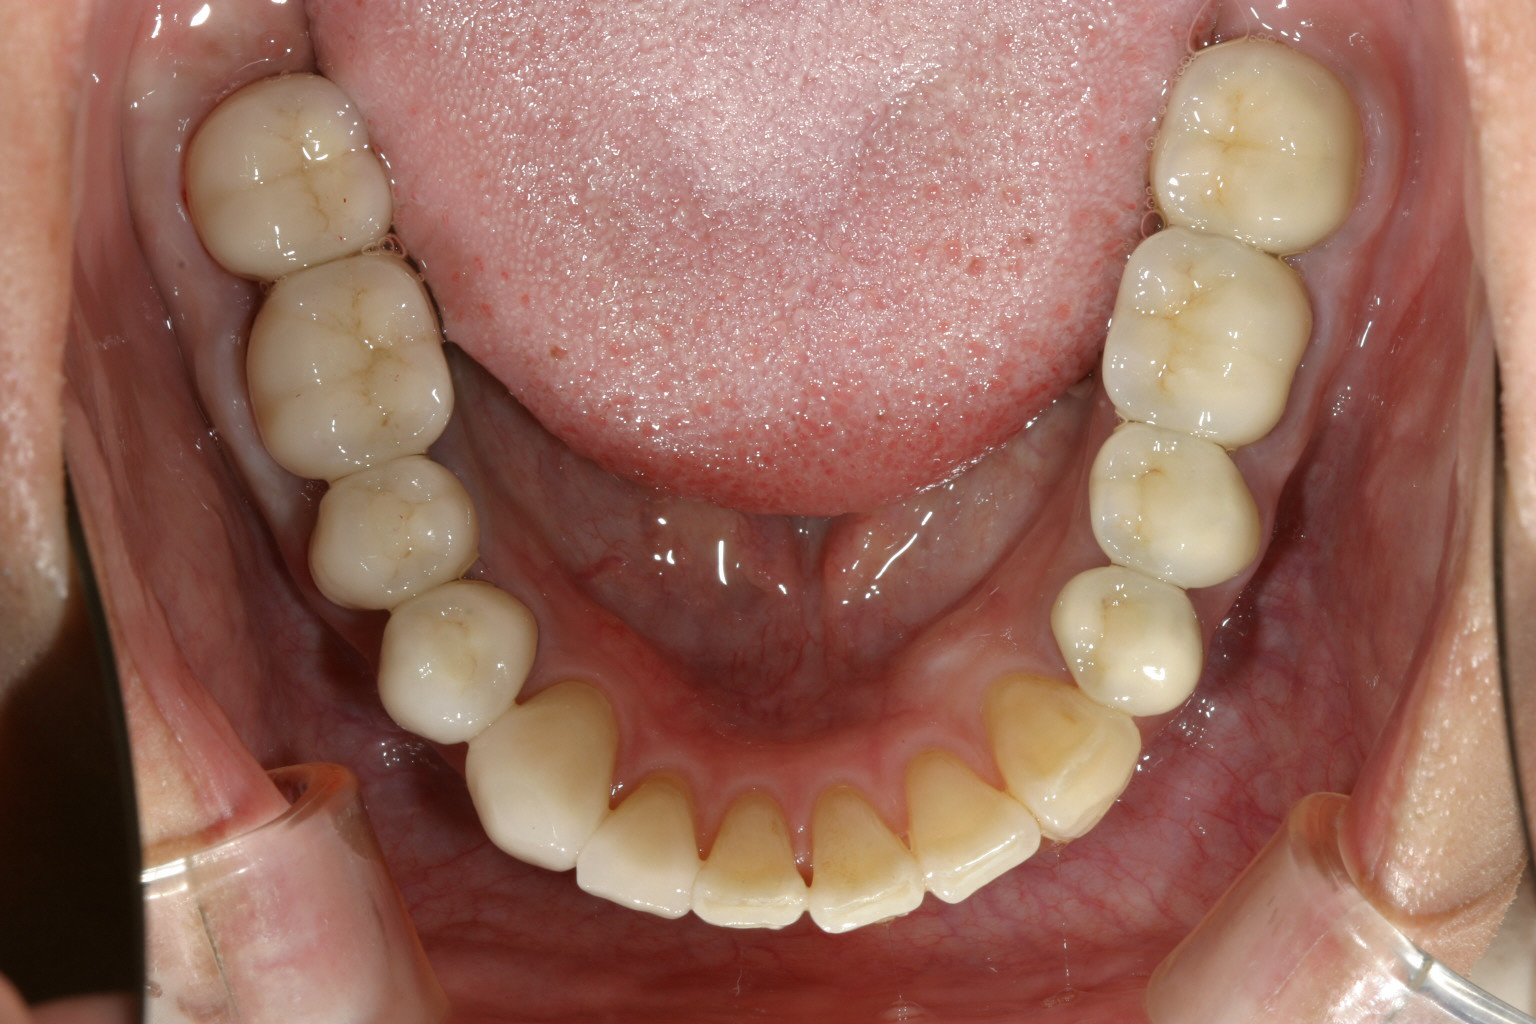

下顎は8本の臼歯を仮歯に変更して顎位を修正したのちマルチループワイヤーにてかみ合わせの調整を行う。 最初右にも左と同様のプラスティックレジン冠を入れるが顎位が右に戻る傾向があり咬耗激しく現在の様な金属冠に変更する。(全体的に少し高さを挙げて特に右側を沢山挙げる事により顎位が左へシフトさせる) アーチフォームもU字変更している。

下顎も矯正による咬合修正も終わり左右臼歯にジルコニア冠で8本補綴完了する